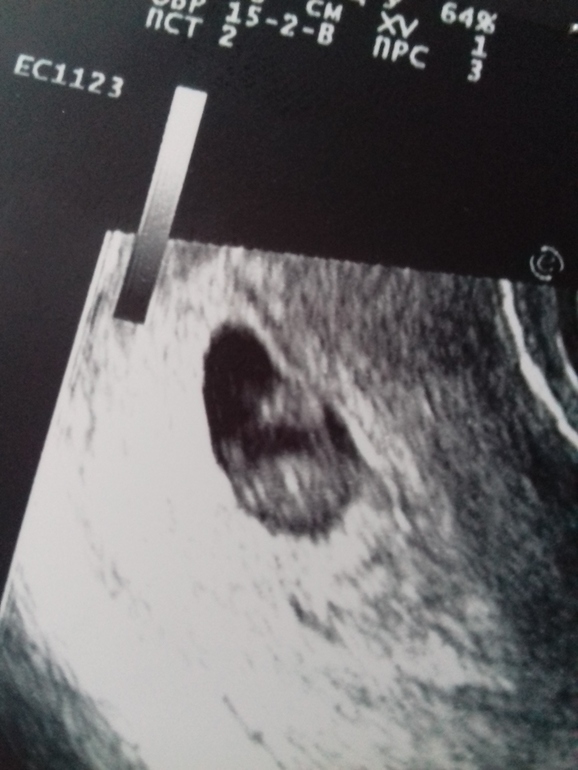

Всё о нашей беременностиПривет любимые! Сходила я на той недельке на узи, увидели малыша и посмотрели сердцебиение. Сиськи болят жутко! Токсикоз опять как в тот раз сильный! Лежу весь день и не могу встать,тошнит! Ничего не охота (((